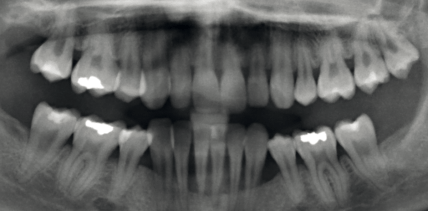

Parodontitis! Eine Erbkrankheit?

Es gibt parodontologisch nichts, was es nicht gibt: Patient/-innen mit relativ guter Mundhygiene können einen rapiden parodontalen Attachmentverlust erleiden, während andere Patienten mit schlechter Mundhygiene kaum parodontale Taschen aufweisen. weiterlesen